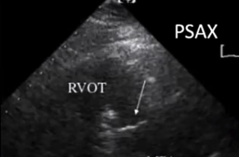

# TTE

- PLAX, PSAX, Subcostal views

左侧胸骨旁(最常用)长轴、短轴,剑突下 - PSAX, standard view for assessment of the PV

胸骨旁短轴,是 PV 评估的标准视图 - Transducer position at base of heart where PA bifurcates

换能器放在心底部 PA 分叉处 - 患者左侧卧位,手放在头部后方

- 探头从胸骨旁长轴切面开始,顺时针 90° 旋转得到主动脉瓣水平短轴切面

- 向上向右肩倾斜,得到改良版的肺动脉瓣水平切面

- 2D Echo (anatomy and structure) 解剖与结构

- PLAX

- PSAX: level of the AV

- Thickened leaflets, doming, calcification

描述瓣叶,增厚、穹隆样改变、钙化 - Variable degree of commissural fusion

不同程度的交界区融合 - Post stenotic dilatation of MPA

狭窄后,肺动脉主干的继发扩张 - RV size is usually normal: as with RVH (>5mm) and RV hypoplasia

右室大小通常是正常的:例如伴右室肥厚 (>5 mm) 和右室发育不良

居中的是主动脉瓣,大概 1-2 点钟方向是肺动脉瓣。PV 看起来有点增厚、钙化,不像正常时的那么薄,有点穹隆样改变,活动有点僵硬,尤其是上方的瓣膜活动度欠佳。右方的肺动脉呈现瓣膜狭窄后继发的扩张(正常应该是小于主动脉部分的尺寸)。